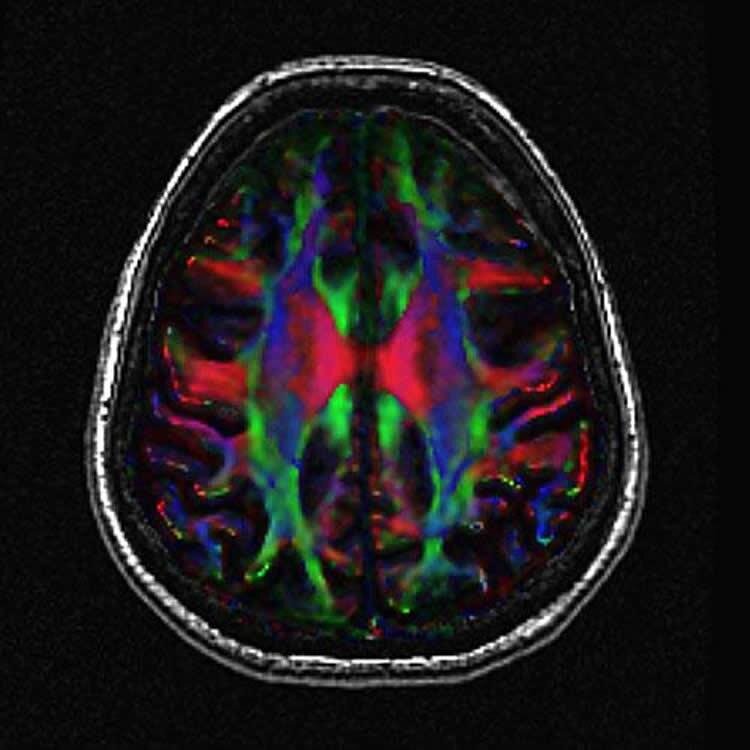

Задняя поясная кора головного мозга (PCC)/область предалинья — это центр нейронных сетей, который интегрирует и рассеивает сигналы. Потеря связи с этим узлом связана с потерей памяти и накоплением амилоида, как признаков MCI, так и болезни Альцгеймера

До и после исследования авторы выполняли участникам функциональную магнитную томографию мозга с целью изучить связи коры задней части поясной извилины и предклинья (PCC/precuneus, эта зона в мозге представляет собой своеобразный информационный хаб) с другими областями, а также провели тест на память (запоминание списка слов).

Данные сканирования оказались весьма интересными: если улучшение способности к запоминанию наблюдалось у обеих групп добровольцев, то только в группе MCI обнаружилось увеличение количества связей между 10 областями мозга, включая лобные, теменные, височные и островковые доли коры, мозжечок и зоной коры задней части поясной извилины и предклинья.